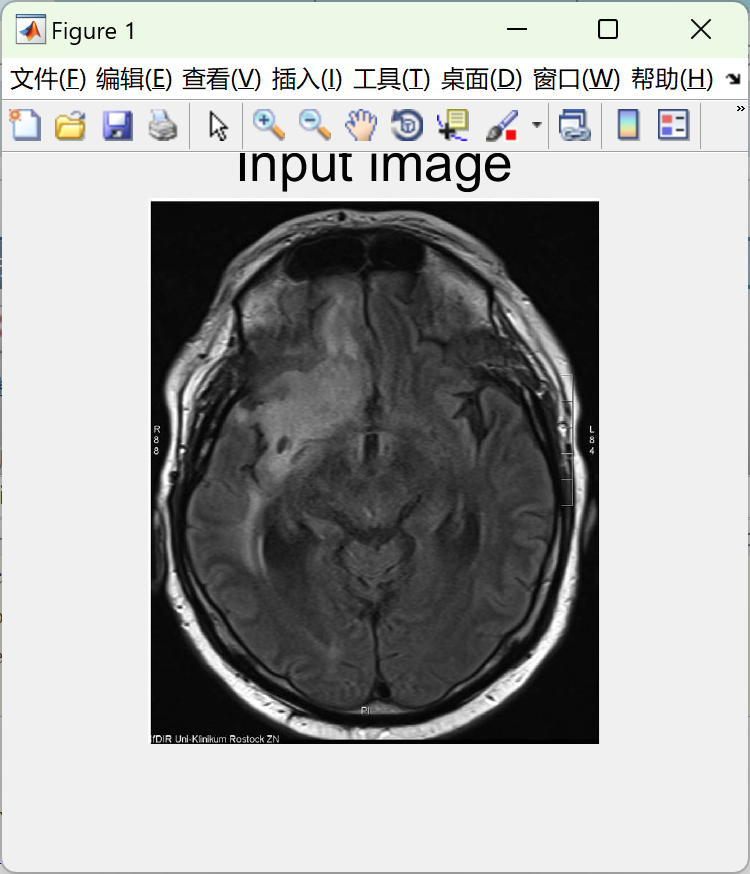

通过磁共振成像(MRI)技术对大脑肿瘤进行检测与分割被视为一项至关重要的医疗任务,它有助于医生更准确地诊断并治疗患者的脑部疾病.首先,从患者头部的MRI扫描中获取高质量的脑部图像数据.这些数据通常包括T1加权、T2加权以及增强T1加权序列等不同类型的医学影像.随后,对原始图像进行预处理,包括噪声去除、图像配准以及标准化处理,以便为后续分析做好准备.在此基础上,利用先进的图像处理技术和机器学习方法对预处理后的MRI图像进行肿瘤检测.这一过程通常涉及提取形态学特征、纹理特征以及基于直方图的方法来识别潜在的肿瘤区域.接着,采用分类器如支持向量机、随机森林或深度学习模型来进行特征分类,以确定肿瘤的具体位置及类型.一旦完成肿瘤区域的识别,下一步便是精确地对其进行分割操作.这一步骤通常采用区域增长算法、边缘检测方法、水平面分割技术或者基于深度学习的分割算法来进行实现.这些算法根据MRI图像中的强度值、纹理特征以及形状信息将肿瘤区域与正常组织区分开来

figure;

imshow(s);

title('Input image','FontSize',20);